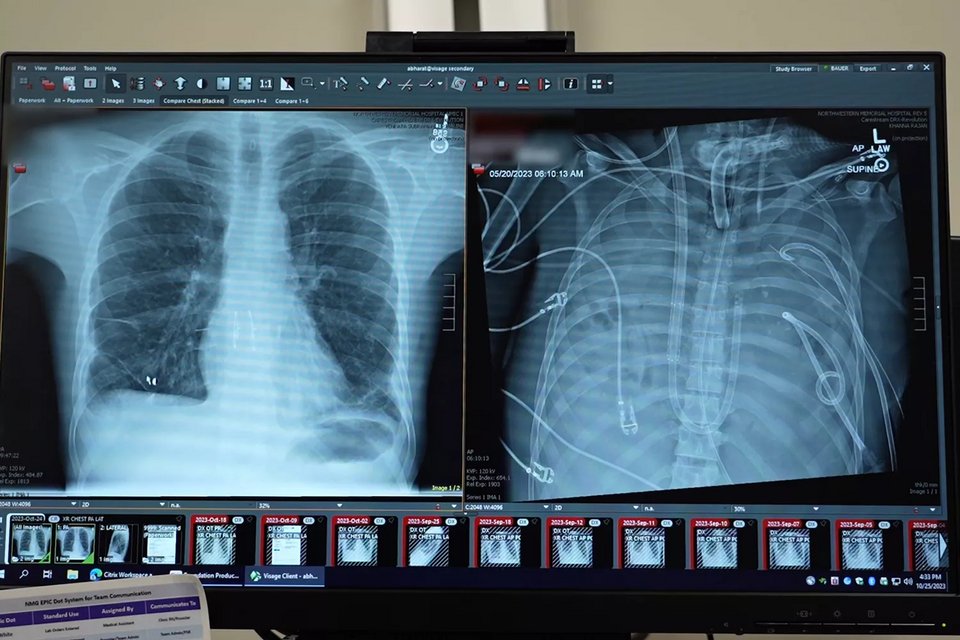

Οι παλιοί πνεύμονες του Bauer (δεξιά) και οι νέοι πνεύμονές του

Οι παλιοί πνεύμονες του Bauer (δεξιά) και οι νέοι πνεύμονές του / Φωτογραφία: NORTHWESTERN MEDICINE